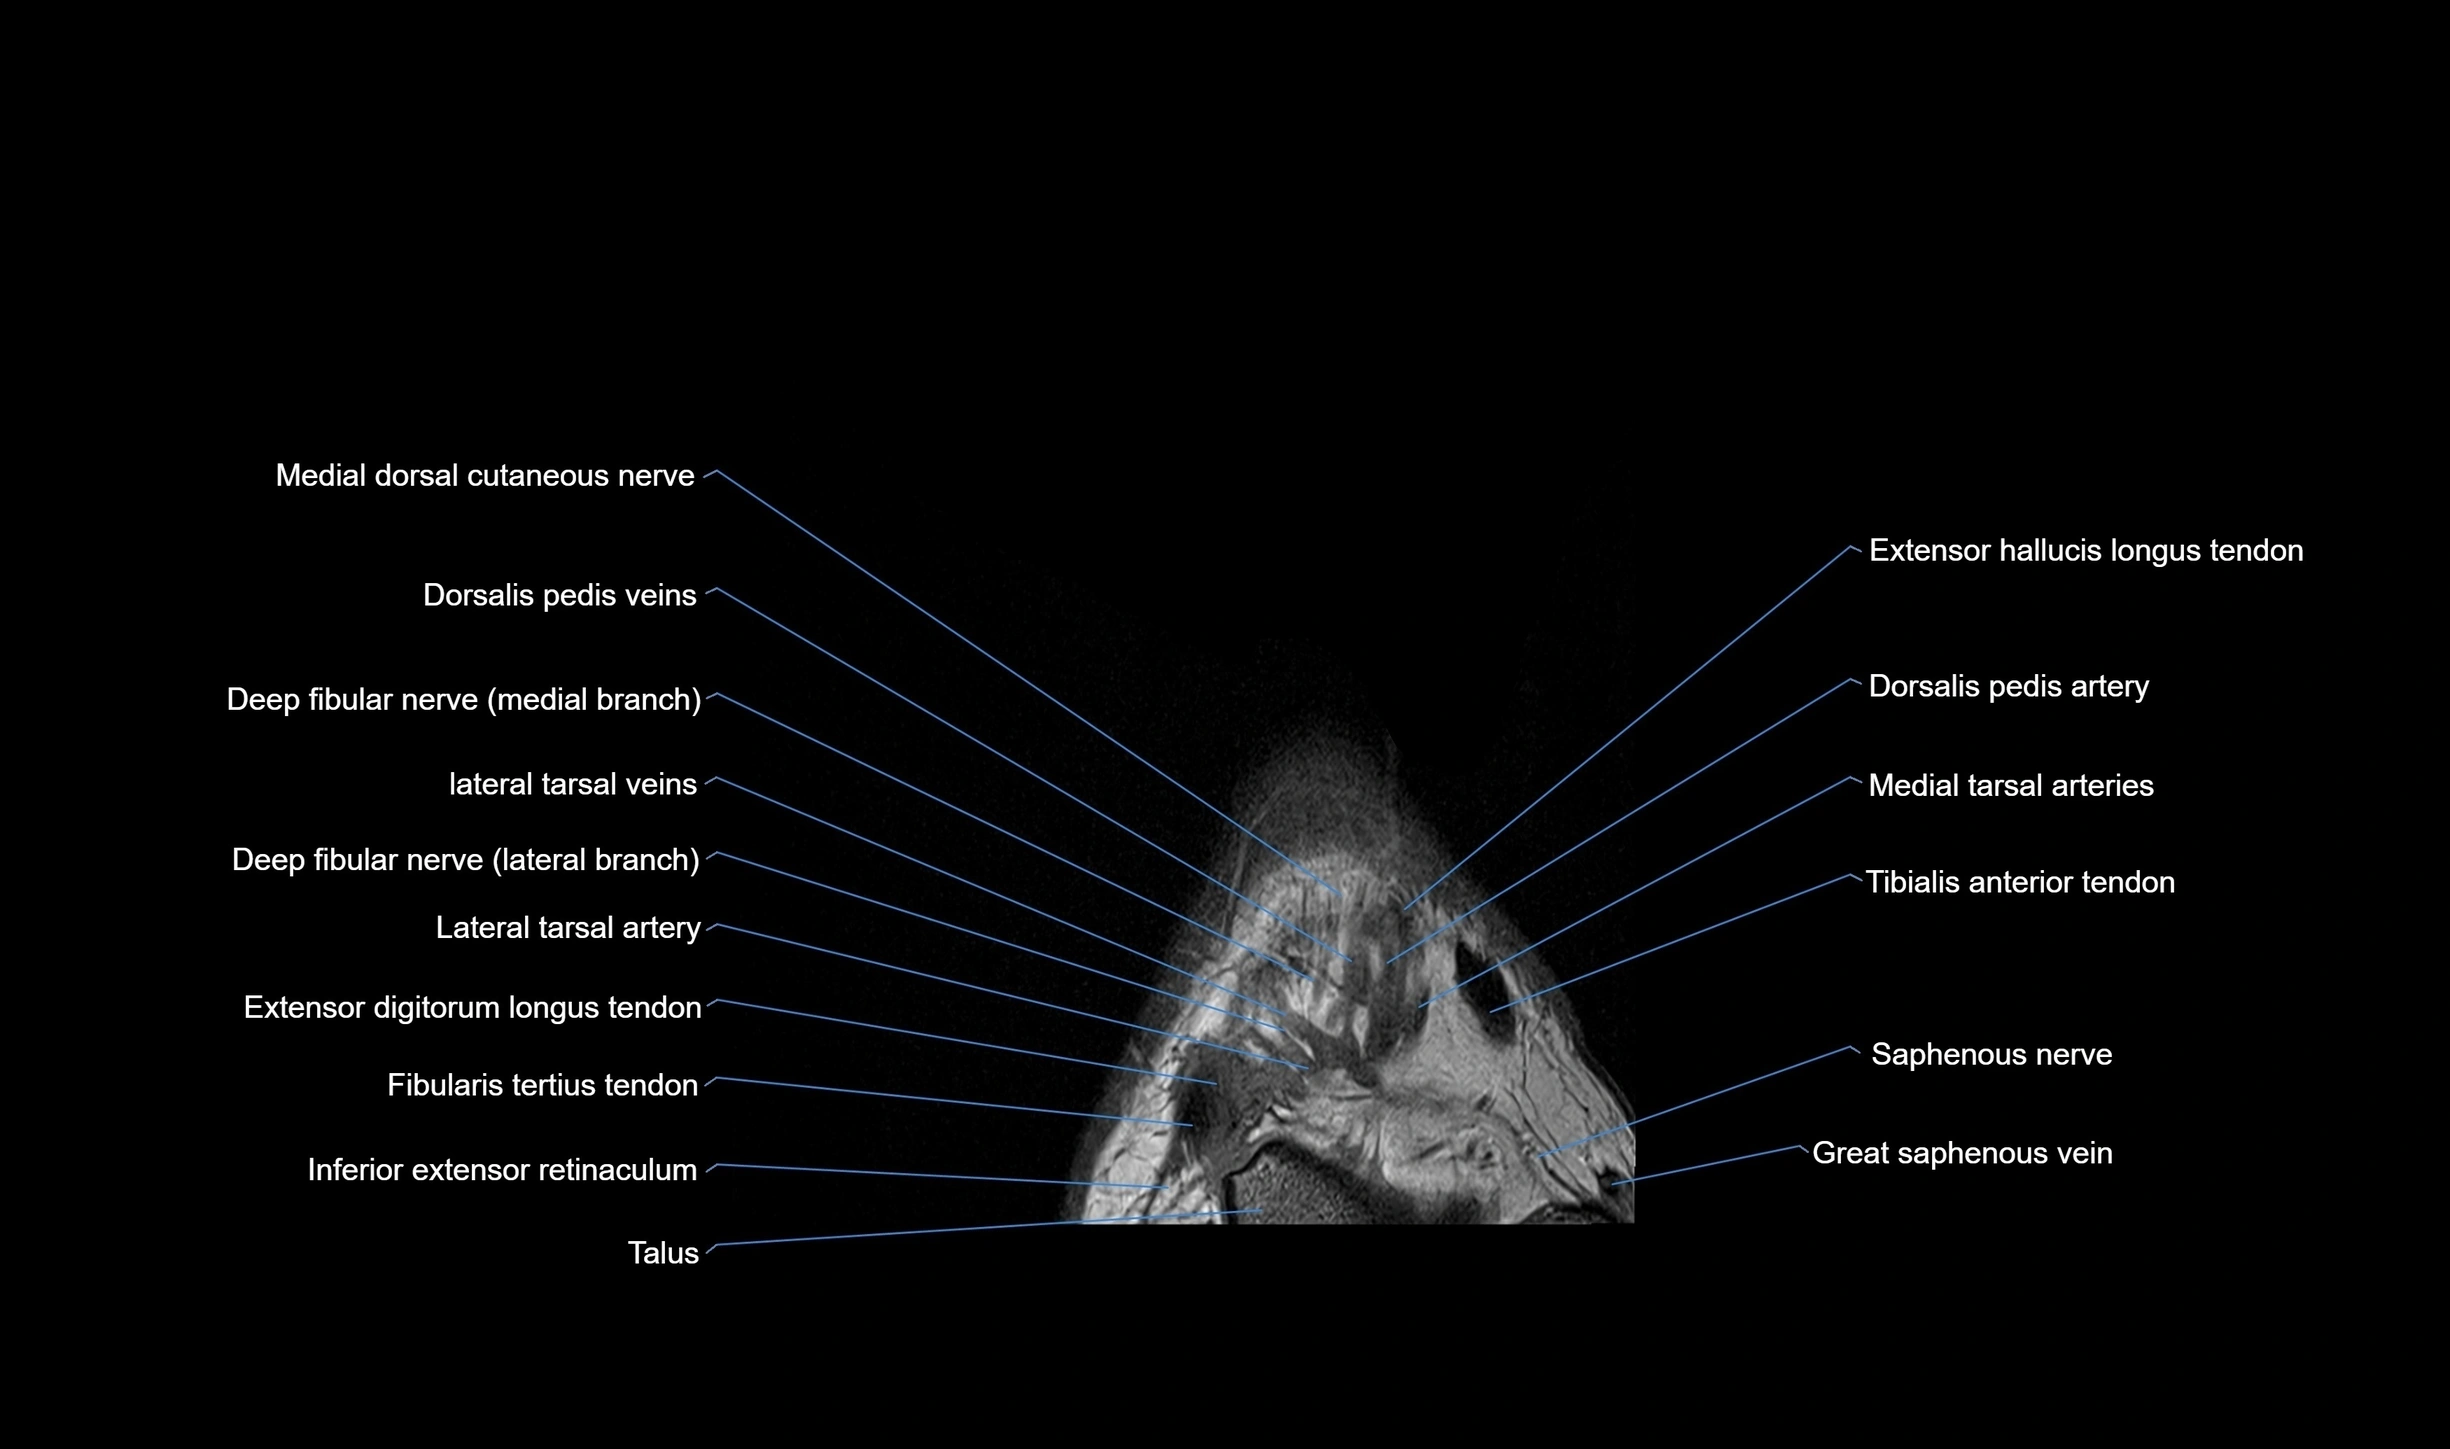

MRI image